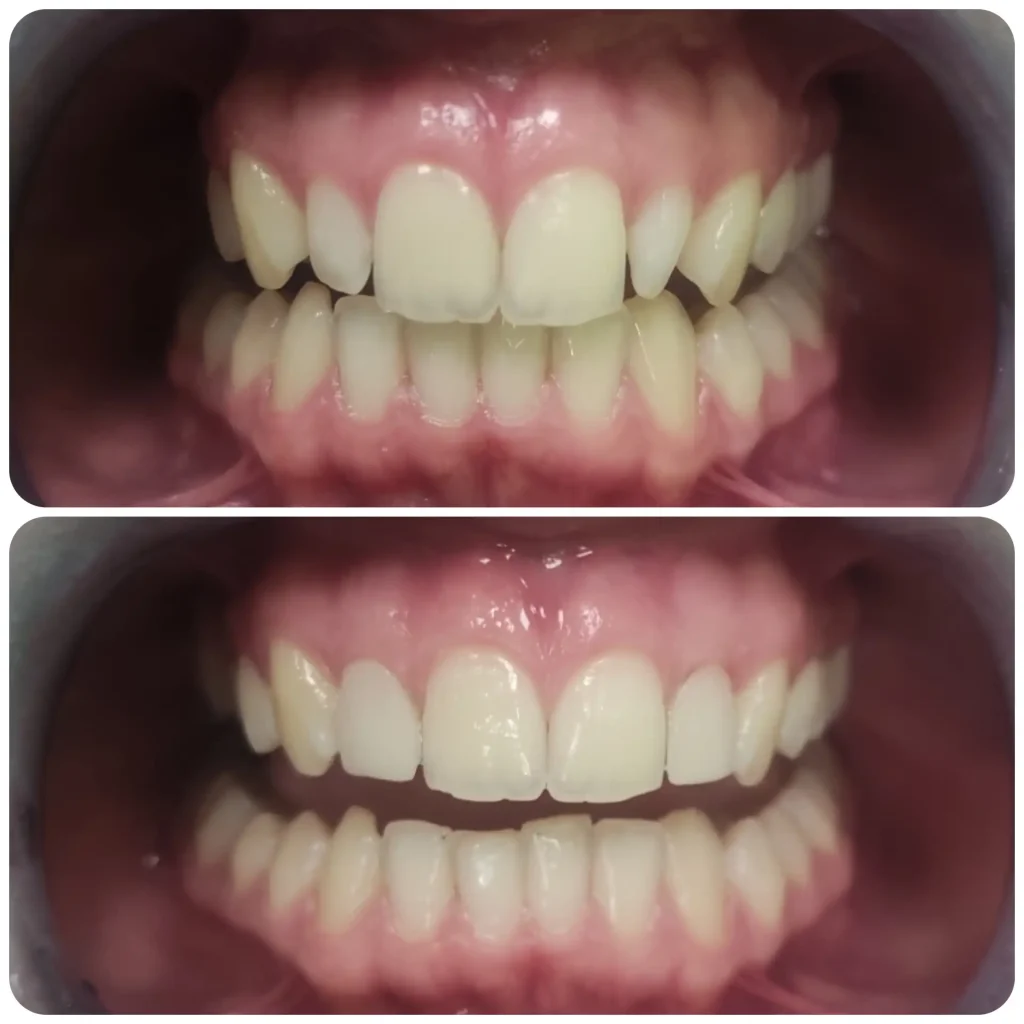

Fő érdeklődési területeim közé tartoznak az esztétikai beavatkozások, tömések, könnyebb gyökérkezelések, hagyományos fogpótlások készítése, kivitelezése. Fontosnak tartom a fogak megfelelő rehabilitációját és szájban tartását. Tudásomat hazai és külföldi szakmai továbbképzésekkel folyamatosan fejlesztem.

Esztétikai és fogmegtartó kezelések mellett nagy érdeklődéssel fordulok a fogszabályozás szakirány felé. Jelenleg fogszabályozási rezidensként sajátíthatom és mélyíthetem el tudásomat a harmonikus és funkcionálisan megfelelő harapás és esztétikai megjelenés kialakításában.